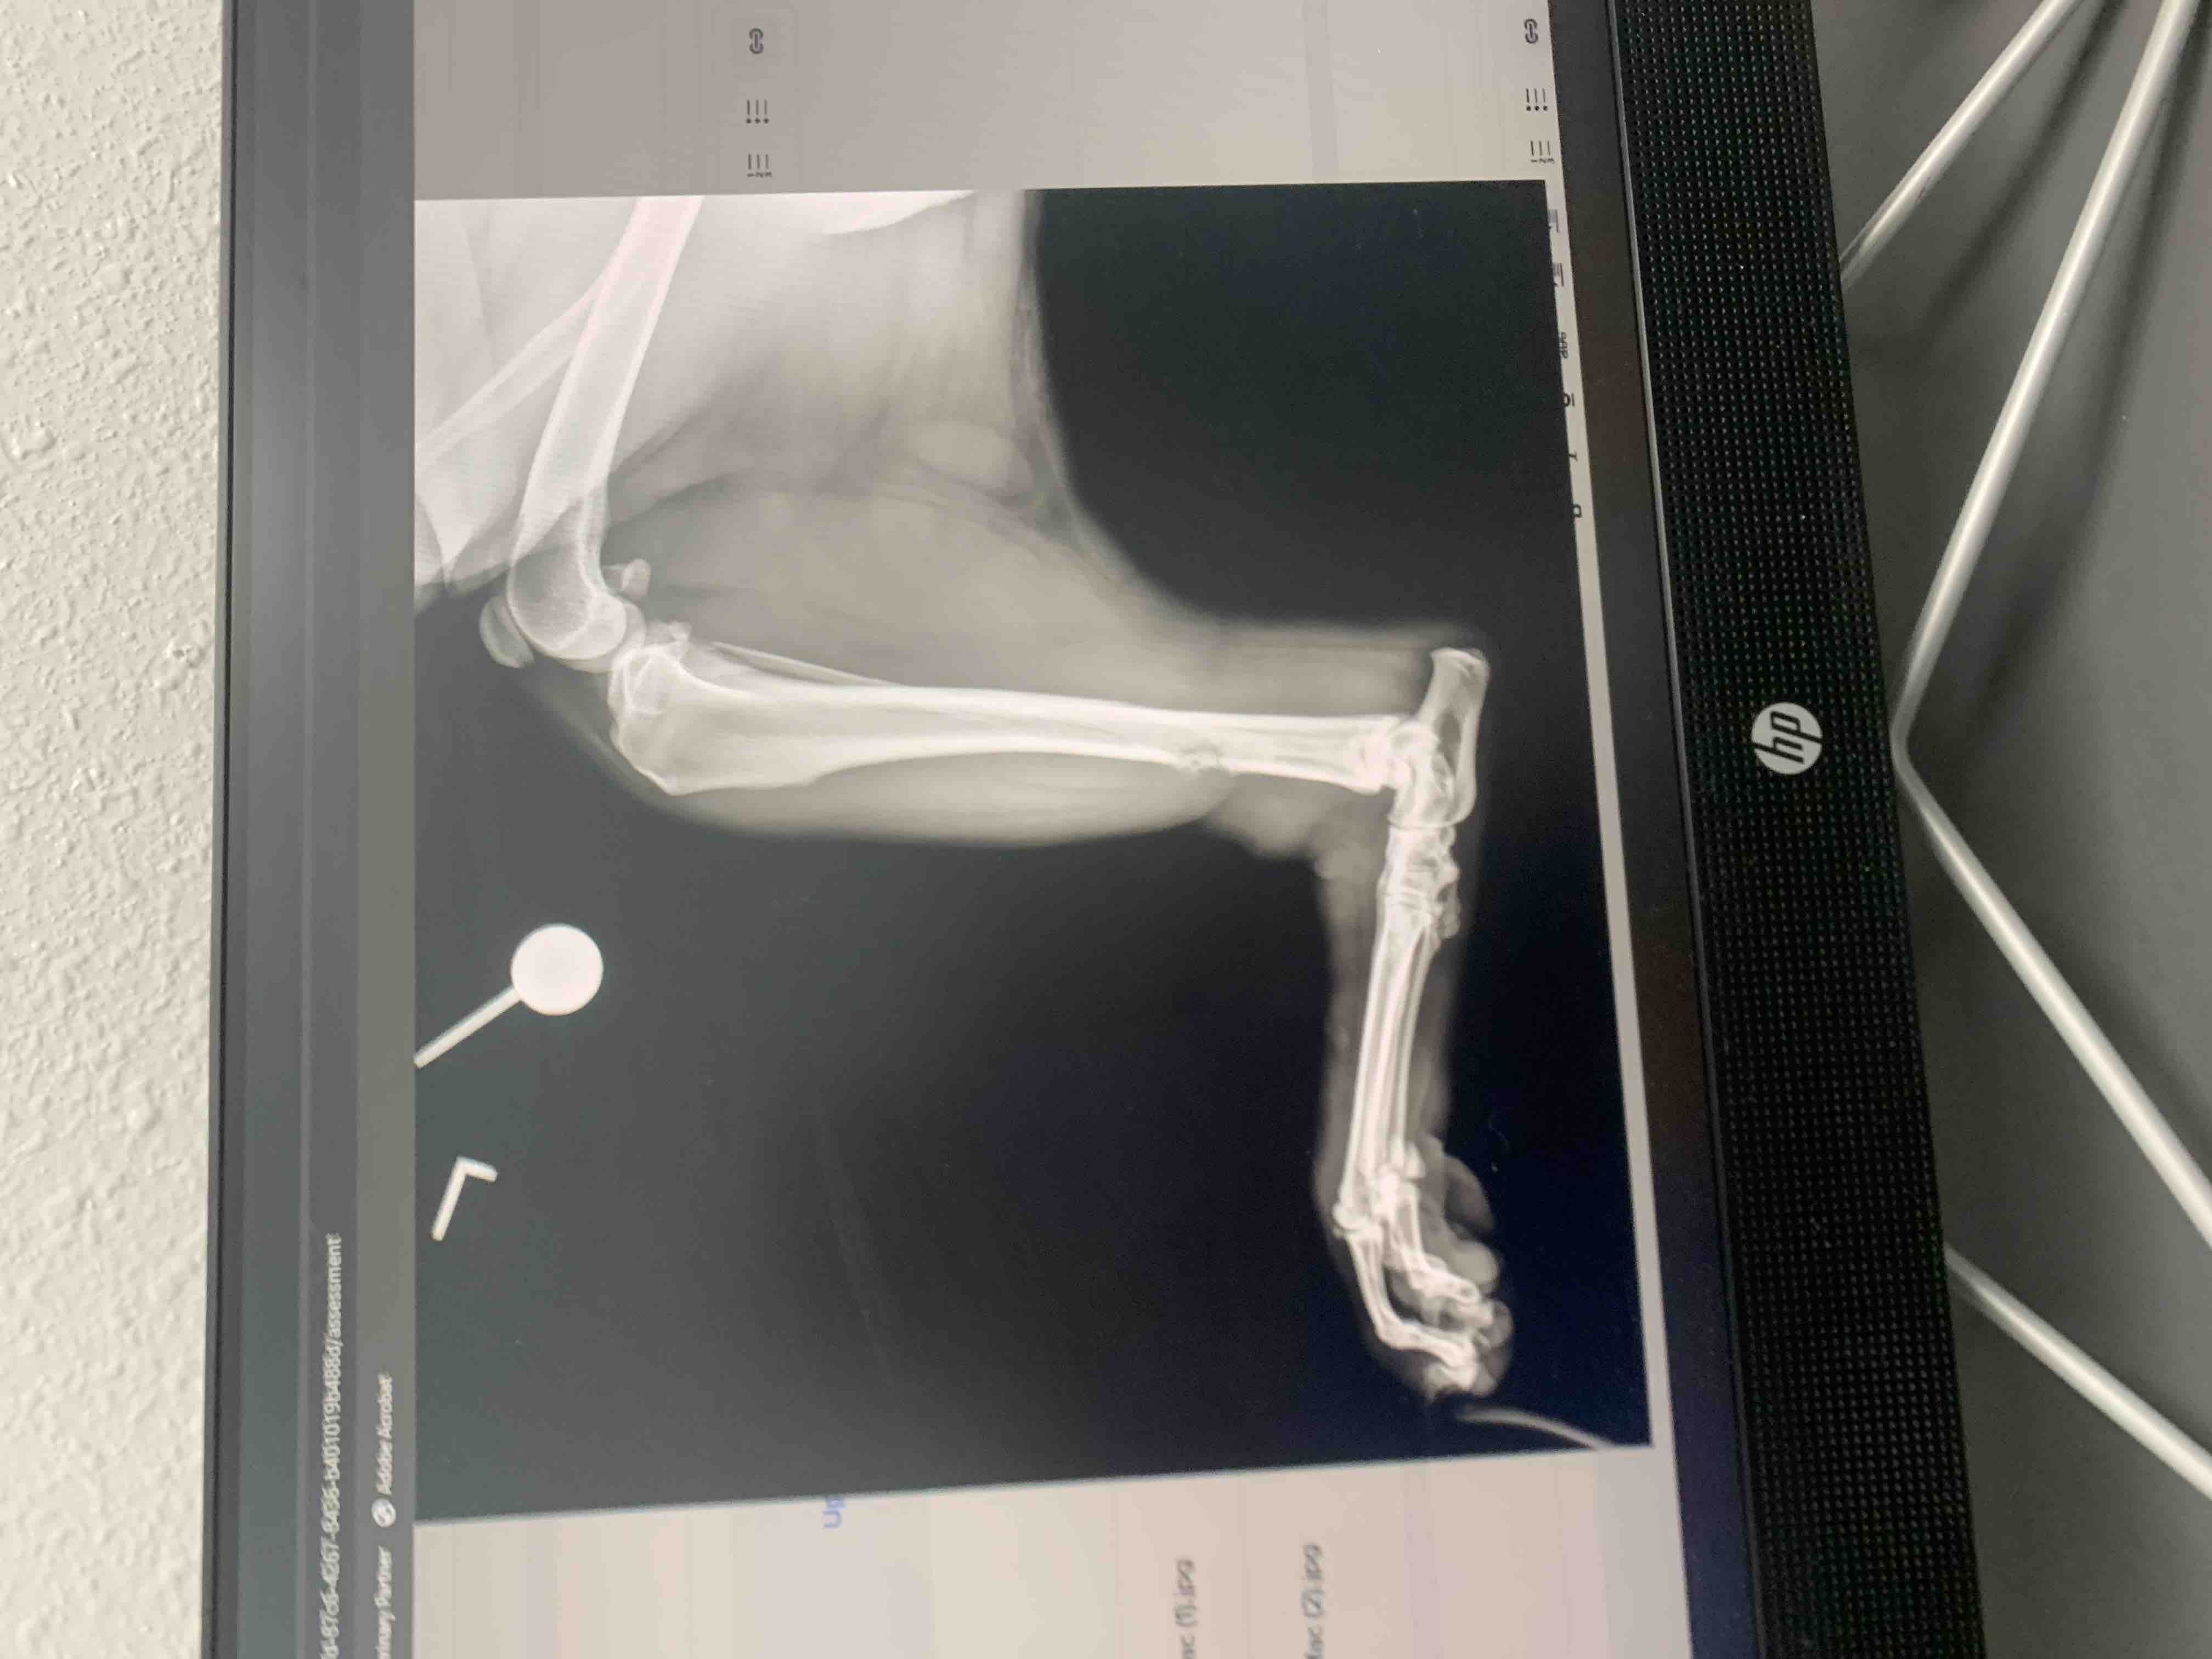

Mac has been a beloved part of our family since he was a puppy. He’s always been full of energy and love, bringing so much joy to our lives every single day. Recently, our world was turned upside down when Mac fractured his leg. After taking him to the vet, we received the heartbreaking news that he also has cancer. The doctors have told us that Mac will most likely need to have his leg removed to give him the best chance at recovery.